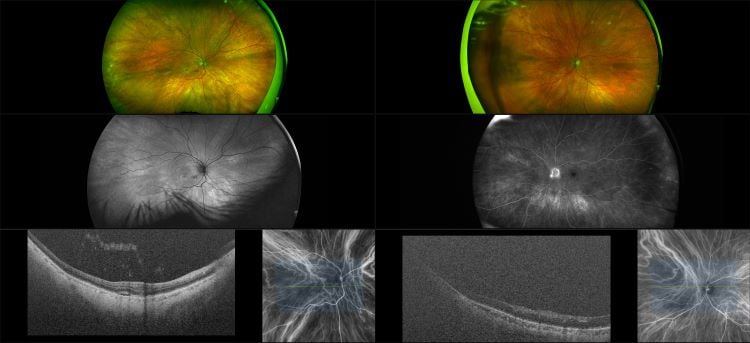

AMD Ryzen 5 1600 AF Review A Wildcard Server Option ServeTheHome best sale, AMD A4 7300 APU Dual Core Radeon CPU Processor HD8470D Graphics FM2 3800Mhz 65W 1MB AD7300OKHLBOX best sale, AMD Ryzen 5 1600 AF 3.2GHz Socket AM4 Box best sale, AMD Ryzen 5 1600 AF Review TechSpot best sale, AMD Ryzen 5 1600 AF Review TechSpot best sale, AMD Ryzen 5 1600 AF Review A Wildcard Server Option Page 3 of 3 best sale, AMD s Ryzen 3 1200 AF the Original Ryzen 3 1200 CPUs Compared best sale, AMD Ryzen 5 1600 AF Review TechSpot best sale, Amazon AMD Ryzen 5 1600 65W AM4 Processor with Wraith Stealth best sale, The US 85 AMD Ryzen 5 1600 AF looks to be a new 12nm Zen part and best sale, AMD Ryzen 5 1600 AF Review TechSpot best sale, AMD s alleged Ryzen 5 3600 AF may give same performance as Ryzen best sale, AMD Ryzen 5 2600X 1600 AF 2024 Revisit vs. 5800X3D 7800X3D best sale, AMD s alleged Ryzen 5 3600 AF may give same performance as Ryzen best sale, AMD A4 3450 Dual Core Processor 2.9 GHz Socket FM1 65W CPU best sale, AMD Ryzen 5 1600 AF Review The Ultimate Value CPU best sale, AMD Ryzen 5 1600 65W AM4 Processor with Wraith Amazon best sale, AMD Ryzen 5 1600 AF Wraith Stealth Edition 3.2 GHz 3.6 Ghz best sale, AMD RYZEN 5 1600 AF 6 Core 12 Threads Max Boost 3.6 GHz best sale, AMD Ryzen 5 1600 AF AM4 12nm eBay best sale, PC Upgrade Kit AMD Ryzen 5 1600 AF MSI B450 TOMAHAWK MAX II best sale, New AMD Ryzen 5 1600 AF CPU Review Benchmarks vs. Original R5 2600 3600 best sale, AMD Ryzen 5 1600 AF UnixBench Whetstone Benchmark ServeTheHome best sale, AMD Ryzen 5 1600 AF Review The Ultimate Value CPU best sale, AMD Ryzen 5 1600 AF 6 Core 3.20GHz 16MB L3 Cache Socket AM4 Processor best sale, File AMD A4 5300.png Wikipedia best sale, Buy AMD Ryzen 3 1200 AF 3.1GHz Quad Core Processor best sale, Replying to Comments AMD Ryzen 5 1600 AF What Is It BIOS Support Memory Controller best sale, AMD s New Ryzen 5 1600 AF Processor Is Cheap AF best sale, AMD Ryzen 5 1600 AF CPU Review Benchmarks Best CPU Under 100 best sale, New AMD Ryzen 3 1200 AF 75 CPU Review Benchmarks Overclocking best sale, AMD Ryzen 5 1600 YD1600BBM6IAF YD1600BBAFBOX best sale, AMD A4 9120C Processors NotebookCheck Tech best sale, AMD Ryzen 5 1600 AF Review TechSpot best sale, AMD Ryzen 7800x3D 64gb DDR5 6000MHZ AMD 7900XT Corsair 5000D best sale, HP 15 AF Laptop Motherboard w AMD A6 5200 2.0GHz CPU best sale, AMD A4 4000 Dual Core Processor 3.0 3.2 GHz Socket FM2 65W CPU best sale, Silverstone Wet AMD Sub Retinal Fluid RG AF FA ICG OCT best sale, AMD YD1600BBAFBOX Ryzen 5 1600 AF Hexa Core 3.2GHz 3.6GHz Boost best sale, AMD A4 4000 Specs TechPowerUp CPU Database best sale, AMD A4 3300 A Series APU CPU GPU Llano Dual Core 2.5 GHz best sale, Xhoba s cpu collection View details on AMD A4 9120C best sale, Performance Preview AMD A4 5000 Kabini Reference Notebook Tested best sale, AMD A4 PRO 7300B 3.8GHz Desktop OEM CPU AD730BOKA23HL best sale, AMD A4 6300 Dual Core 3.70GHz FM2 CPU Processor AD630B0KA23H best sale, AMD RYZEN 5 1600 AF 6 Core 12 Threads Max Boost 3.6 GHz best sale, AMD s New Ryzen 5 1600 AF Processor Is Cheap AF best sale, AMD Ryzen 5 1600 AF Review TechSpot best sale, AMD A4 6300 Dual Core 3.70GHz FM2 CPU Processor AD630B0KA23H best sale, Gateway 11.6 best sale.